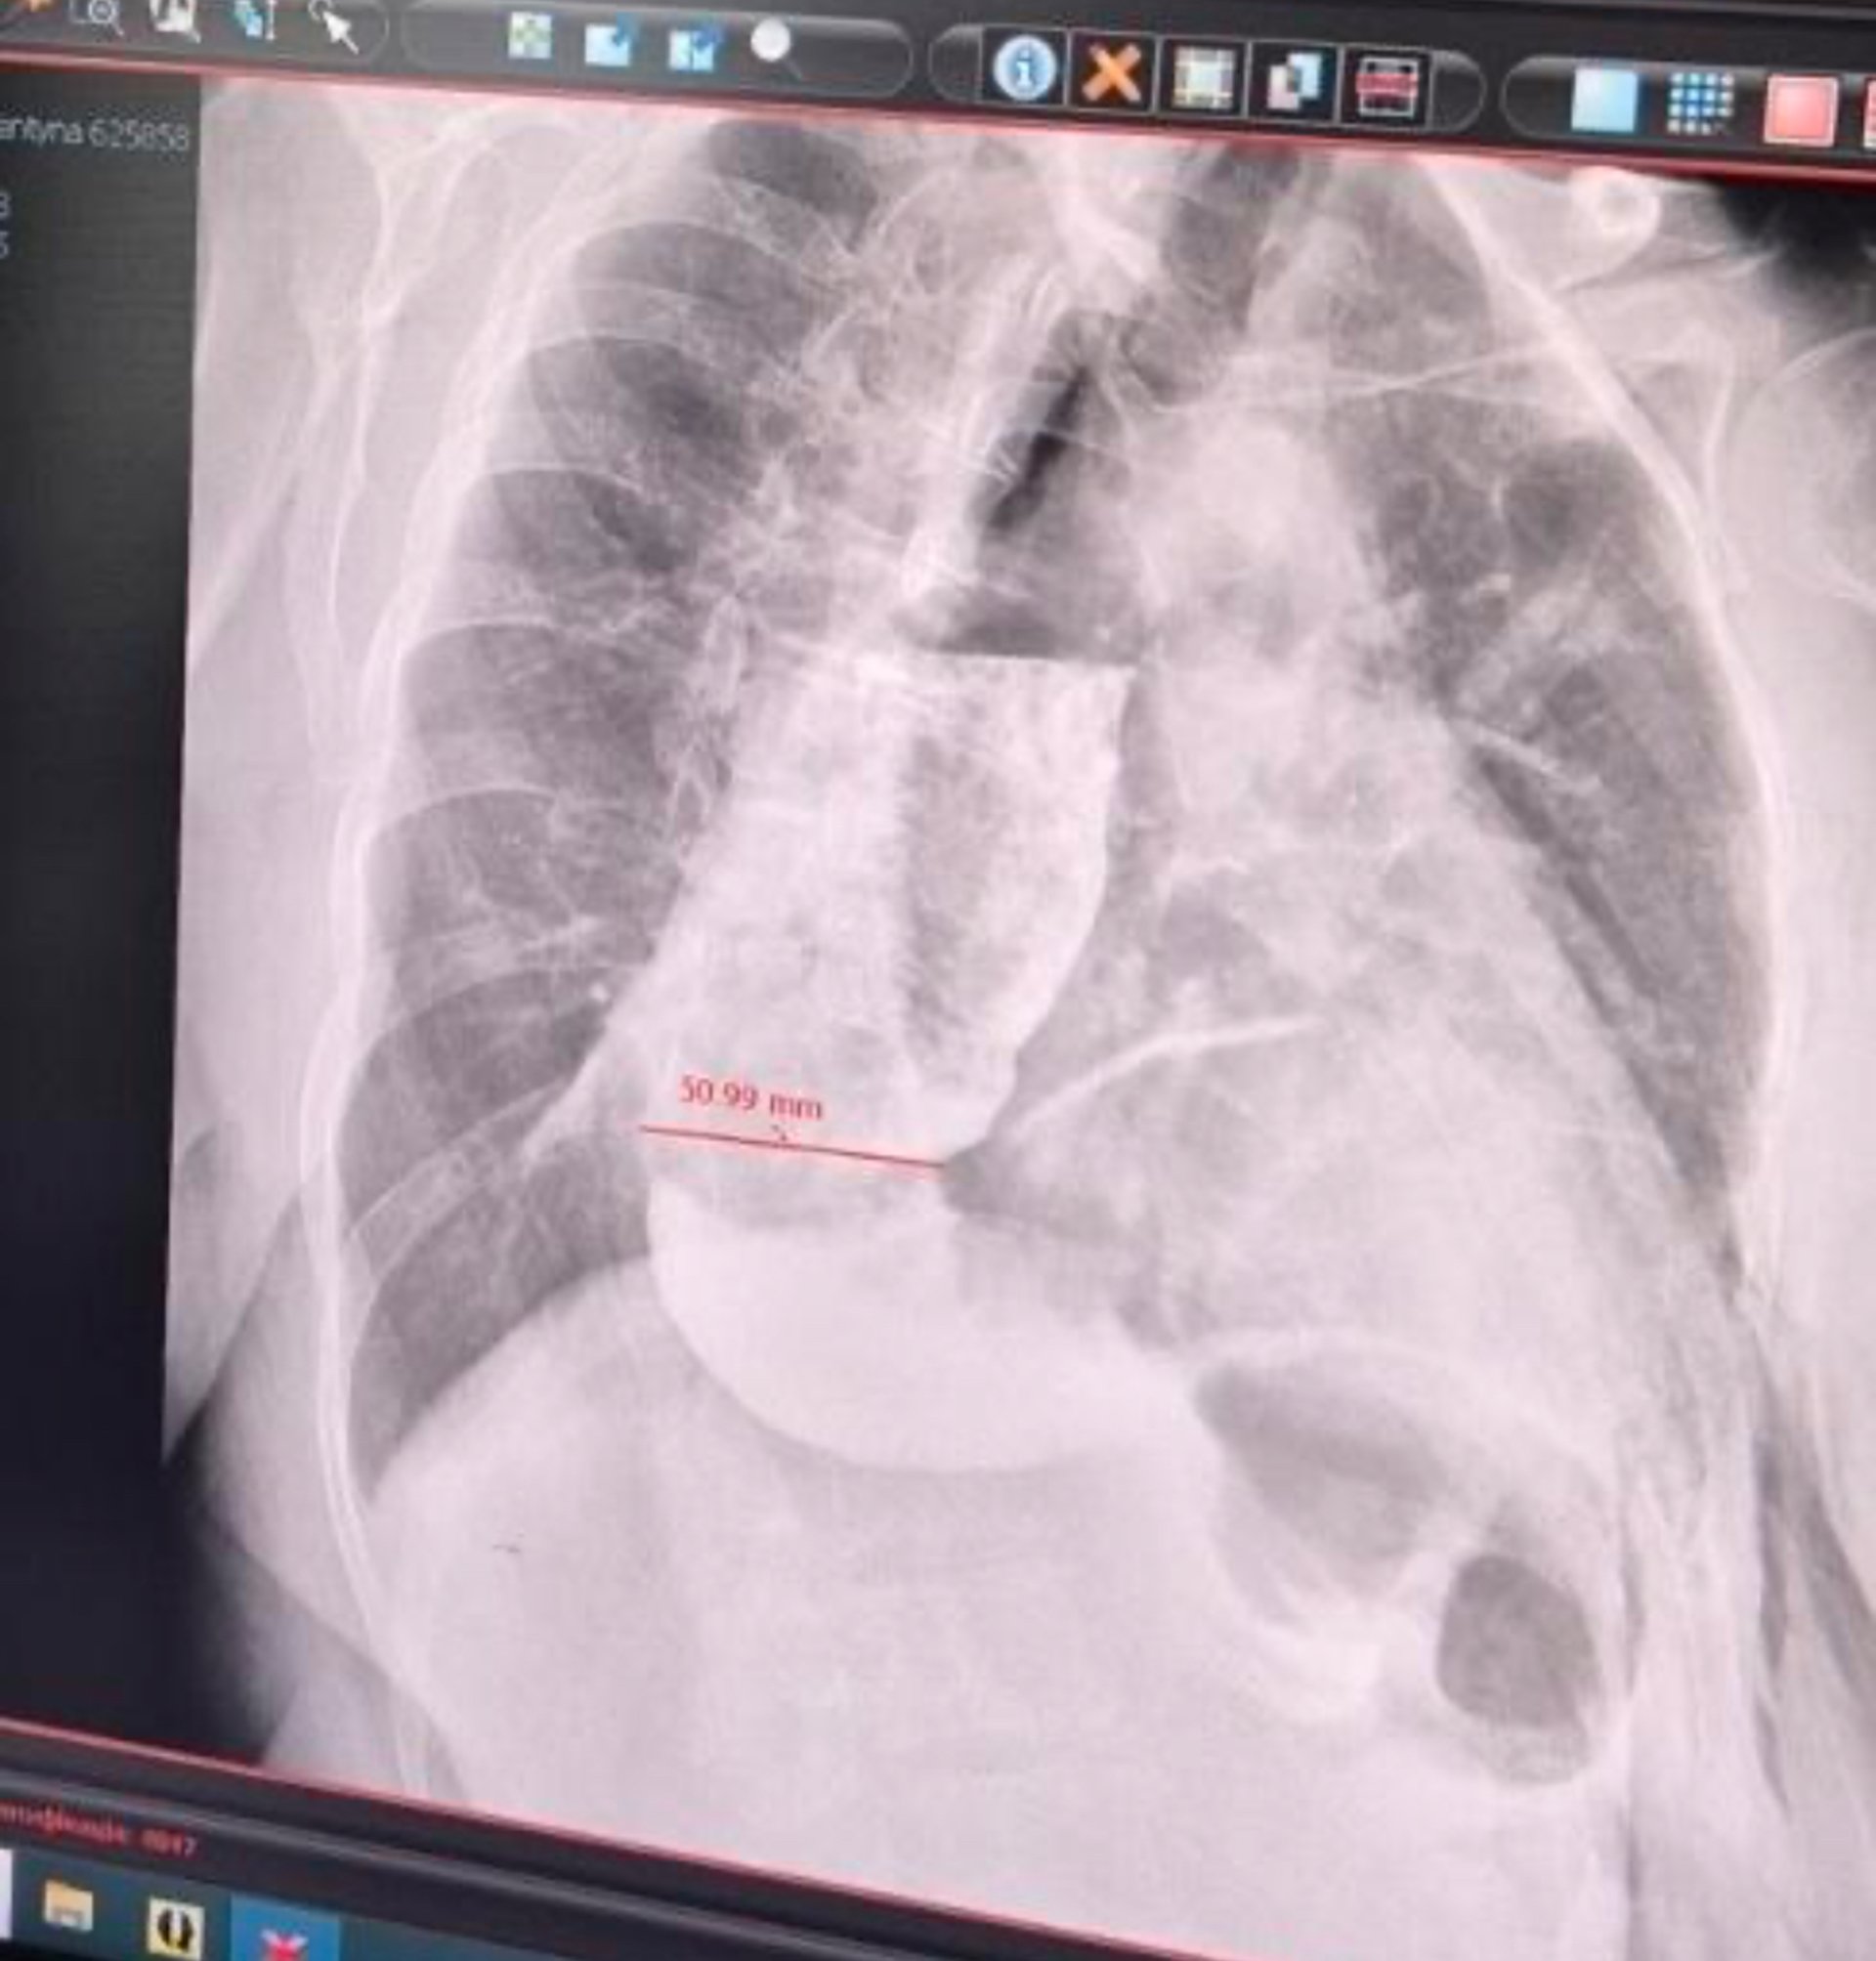

Після обстеження лікарі діагностували у Валентини ахалазію кардії стравоходу – рідкісне захворювання, що зустрічається лише у 2 людей на 100 тисяч. Фахівці пояснили: "Ахалазія – це розлад моторики травної системи, що характеризується порушенням релаксації нижнього стравохідного сфінктера. Простими словами: клапан, через який їжа надходить у шлунок, спазмований і рефлекторно не відкривається. Їжа накопичується у стравоході і розтягує його. В нормі діаметр органу має становити до 3 сантиметрів, тоді як у пані Валентини він був уже цілих 7".